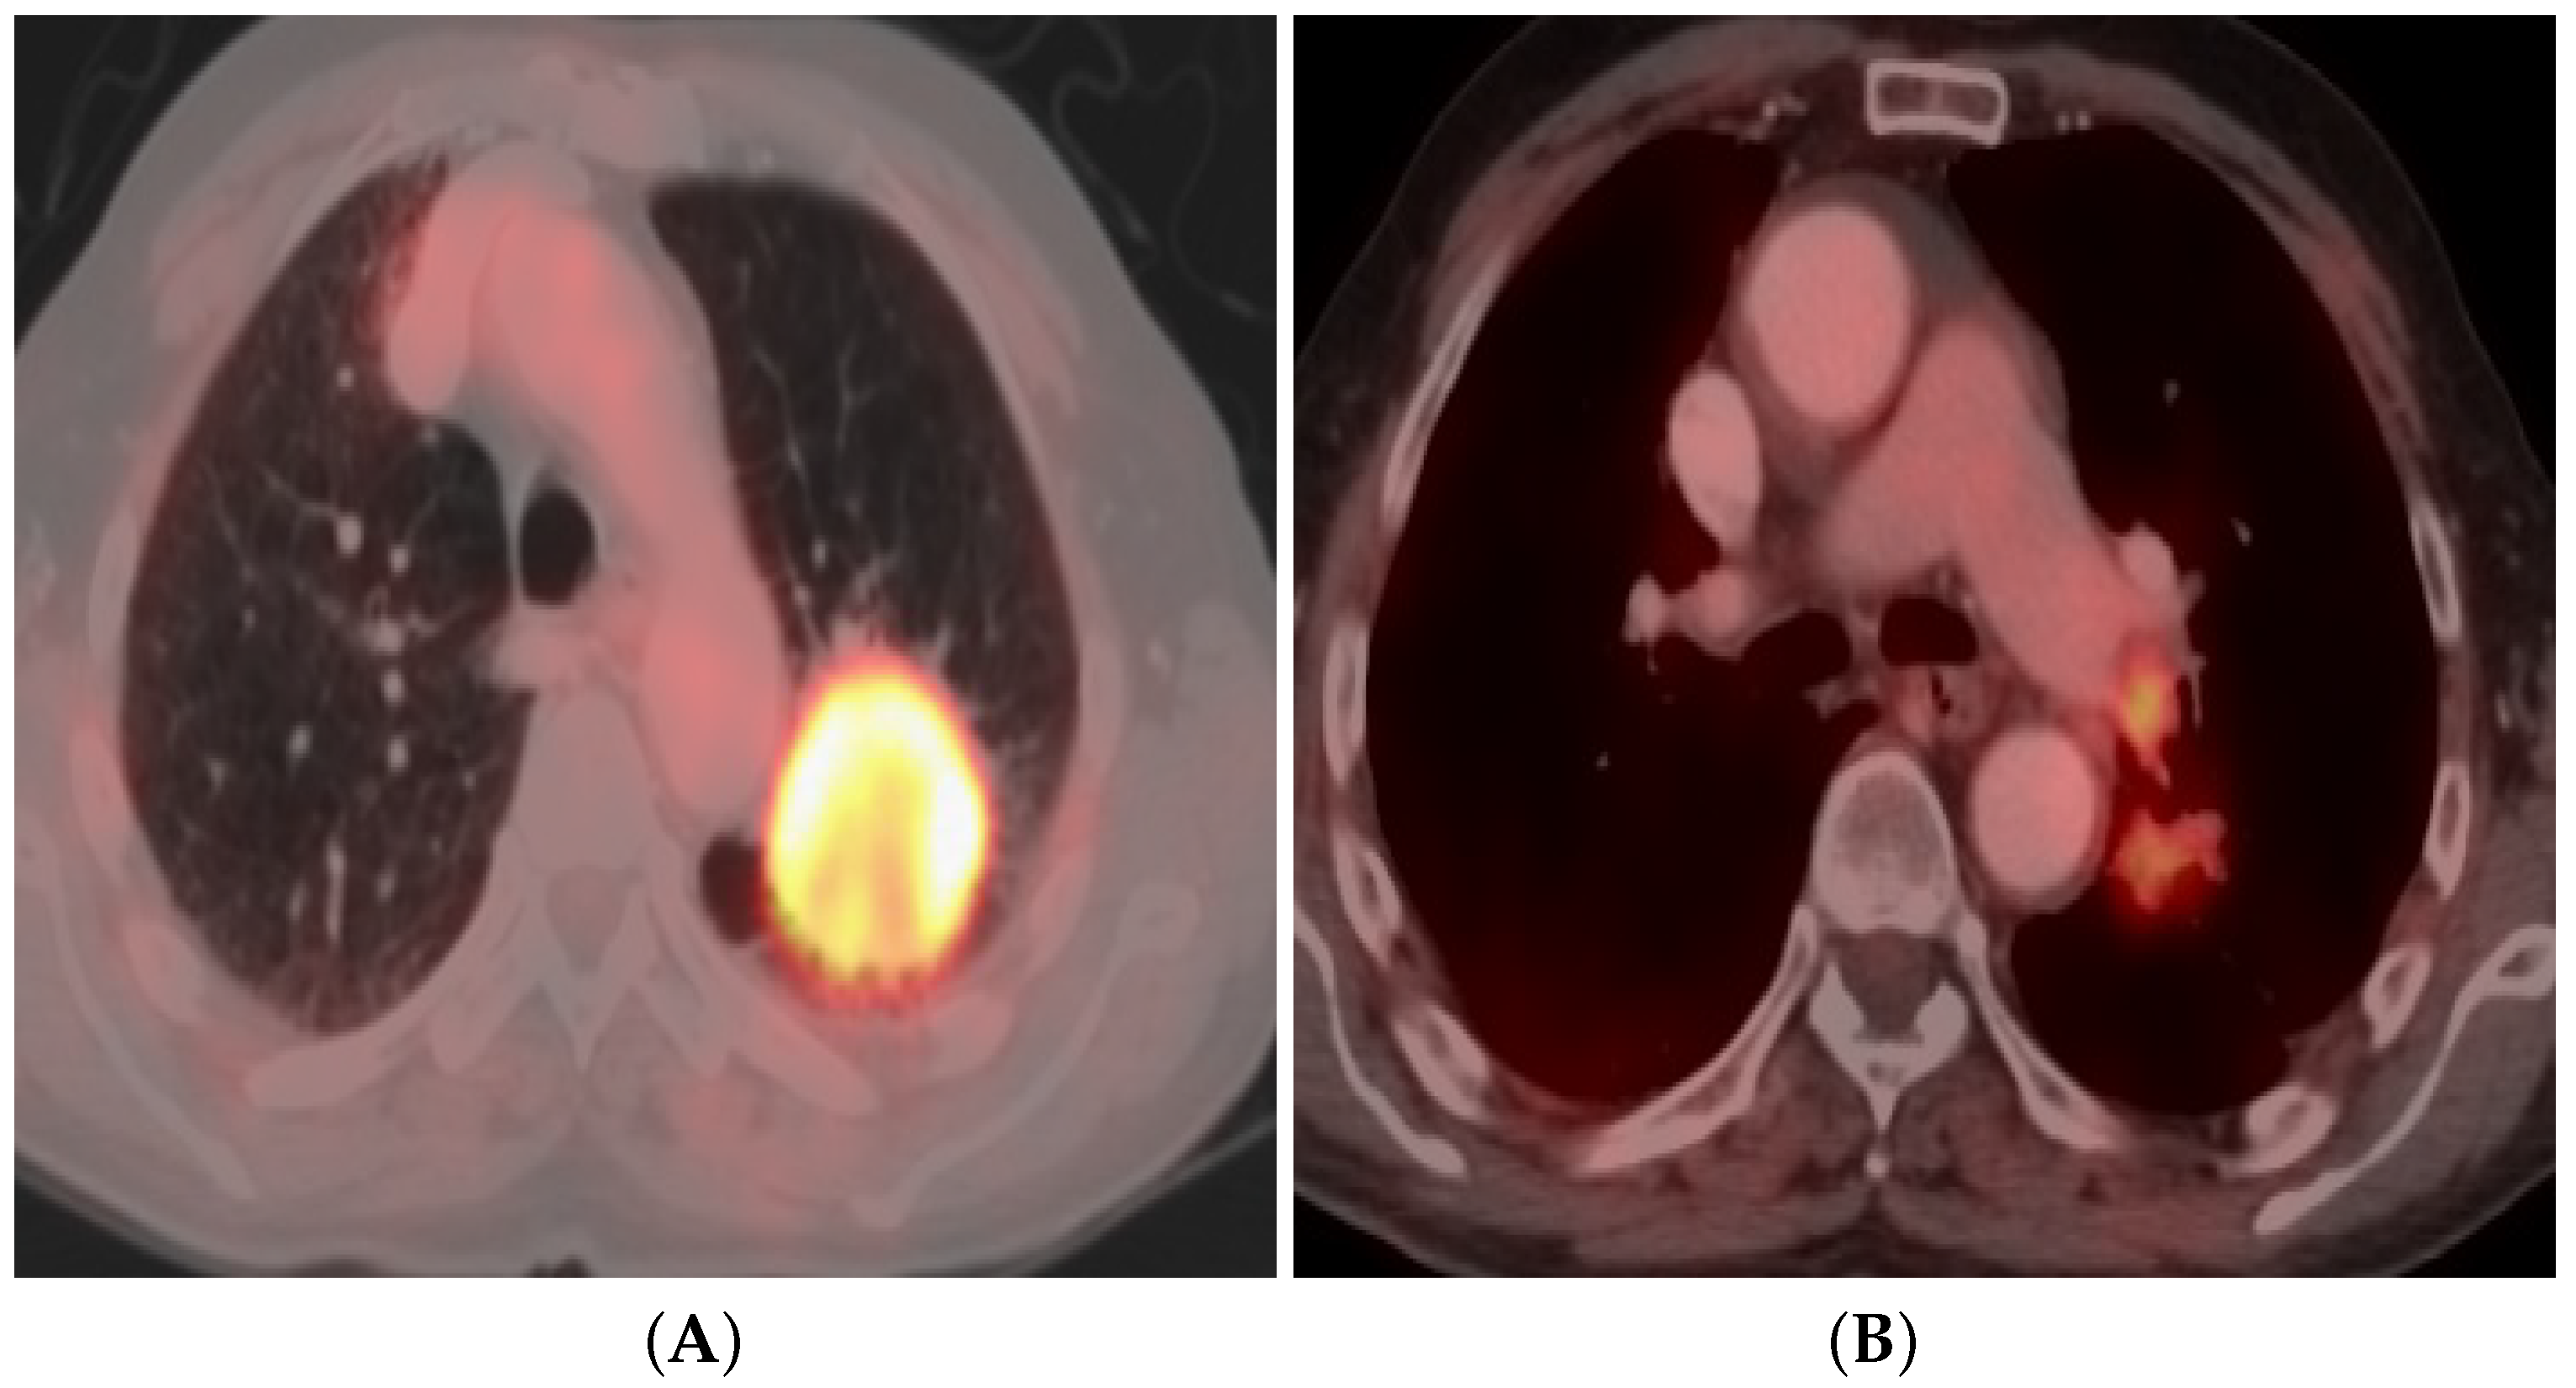

3.4. Positron Emission Tomography (PET/CT)

3.4.3. Qualitative Image Analysis

3.4.4. Quantitative Image Analysis

3.4.5. PET/CT Imaging Pitfalls

3.4.6. Dual-Time-Point FDG PET/CT

3.4.7. DTP FDG PET/CT Scan Acquisition